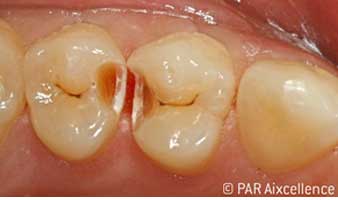

Abb 3: Bei der Anfangseröffnung ist die Karies deutlich klinisch sichtbar.